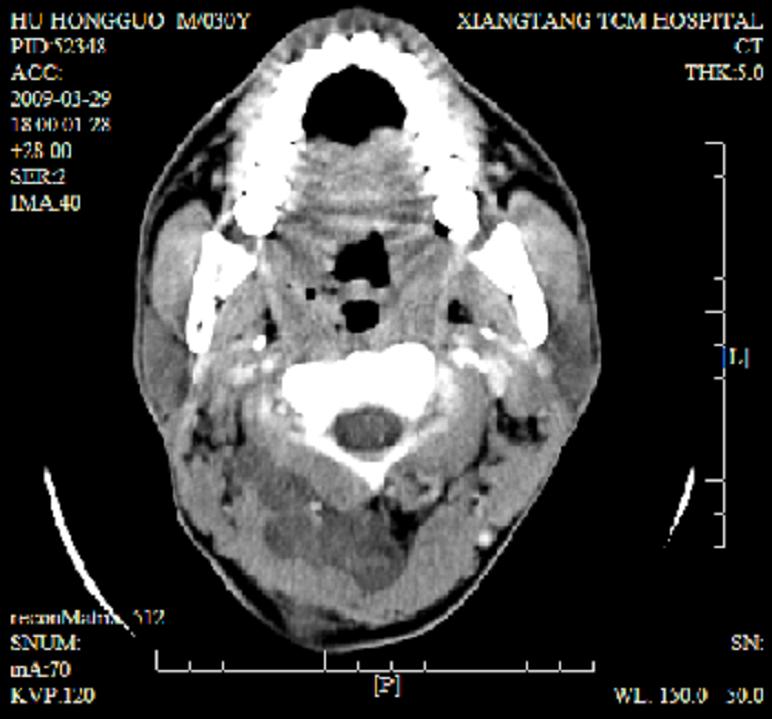

标题: CT19102:颈部肿块

男30y发现肿块3年

多处囊实性肿块,形态欠规则有一定形态,内见点状钙化,以囊变为主,增强后轻度强化,首先考虑神经源性肿瘤如鞘瘤,不除外脉管源性肿瘤如淋巴管瘤(见缝钻及囊性区域太多,如果合并感染完全可以这个影像表现),和海绵状血管瘤,但是血管瘤不太支持因为强化特征和病灶形态不典型.

右侧椎前间隙后部肌间、皮下囊性为主病变,可见分隔和点状钙化,分隔和壁呈轻度环形强化,大部分无强化。形态不规则,有钻缝特点。考虑1 淋巴管瘤合并感染2 血管平滑肌脂肪瘤3 表皮样囊肿4 不除外海绵状血管瘤。